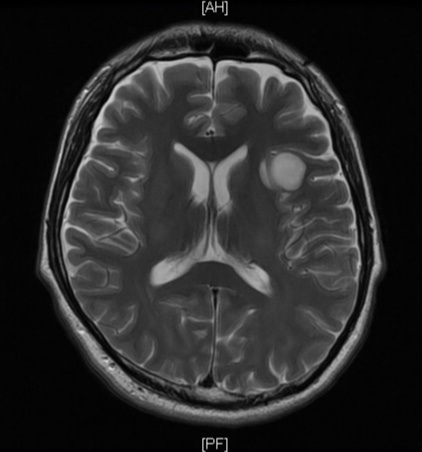

| 診断 | 触診で肋骨の下に固い感触があったためエコーで検査したところ、15cm級の腫瘤があるとのこと。肝臓や腎臓からは分離して見えるらしい(境界がはっきりしているので浸潤はなく良性腫瘍と思いたい)。大病院で診てもらったほうが良いとのことで、地元で大きな病院へ紹介してもらった。 大病院での診断ではすぐに摘出したほうが良いとのことで、コロナ禍かつゴールデンウィーク前のややこしい時期であったが手術をねじ込んでくれた。 なお、病理検査前の診断は「GISTの疑い」であった。 | 脳神経外科でめまいに関する検査を受けたが特に異常は無し。念のため頭部MRIを撮っておこうとなり、予約して後日検査したところ脳に直径22mmの腫瘍があることが発覚(ただし、めまい症状とは関係ないとのこと)。1か月後に再度造影剤ありのMRIを撮り、拡大がないことから悪性度は低いとの見立て。言語中枢に近いところに腫瘍があるため除去には覚醒下手術が必要で、この手術ができる大学病院を紹介してもらった。 さすがにヤバそうな病気のためセカンドオピニオンを受けたが同様の診断であった。 当初紹介された大学病院で診てもらい、摘出手術を受けることになった。 【備忘録】グリオーマ・びまん性星細胞腫:脳腫瘍が発覚した経緯2 |